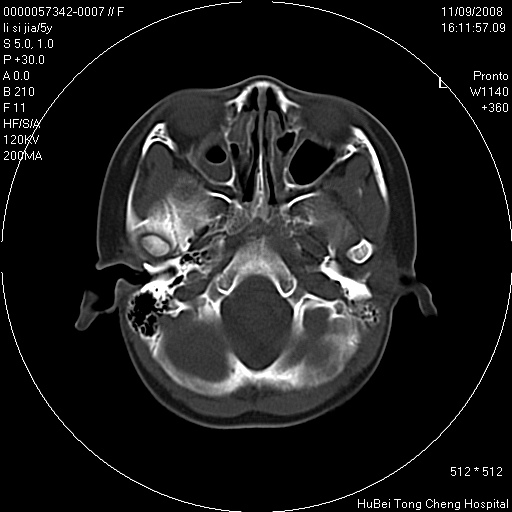

患儿 女,5岁。鼻塞、流涕2年余。

临床诊断:慢性副鼻窦炎?

副鼻窦ct轴位平扫(层厚、层距均为5mm),图像如下:

双侧上颌窦\\筛窦及蝶窦内均可见多量软组织密度影,结合病史支持考虑慢性全鼻窦炎

双侧上颌窦、筛窦及蝶窦内均可见粘膜增厚,结合病史支持考虑慢性全付鼻窦炎,腺样体肥大。